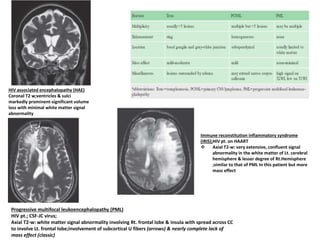

HIV associated encephalopathy (HAE)

Coronal T2 w;ventricles & sulci

markedly prominent-significant volume

loss with minimal white matter signal

abnormality

Progressive multifocal leukoencephalopathy (PML)

HIV pt.; CSF-JC virus;

Axial T2-w: white matter signal abnormality involving Rt. frontal lobe & insula with spread across CC

to involve Lt. frontal lobe;involvement of subcortical U fibers (arrows) & nearly complete lack of

mass effect (classic)

Immune reconstitution inflammatory syndrome

(IRIS);HIV pt. on HAART

 Axial T2-w: very extensive, confluent signal

abnormality in the white matter of Lt. cerebral

hemisphere & lesser degree of Rt.Hemisphere

;similar to that of PML In this patient but more

mass effect